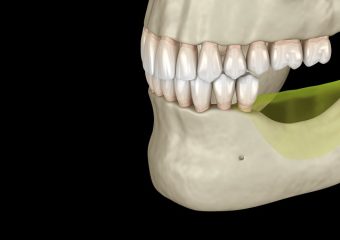

- بررسی تصاویر رادیوگرافی و سی تی اسکن در ابتدا دندانپزشک متخصص با کمک سی تی اسکن و رادیوگرافی، به بررسی وضعیت دندانها و لثه میپردازد. وی برای پیوند استخوان، عمق و عرض استخوان را به طور دقیق ارزیابی میکند.

- کنار زدن بافت لثه دندانپزشک میتواند با جدا کردن لثه از دندان، به ریشه و استخوان دندان دسترسی پیدا کند.